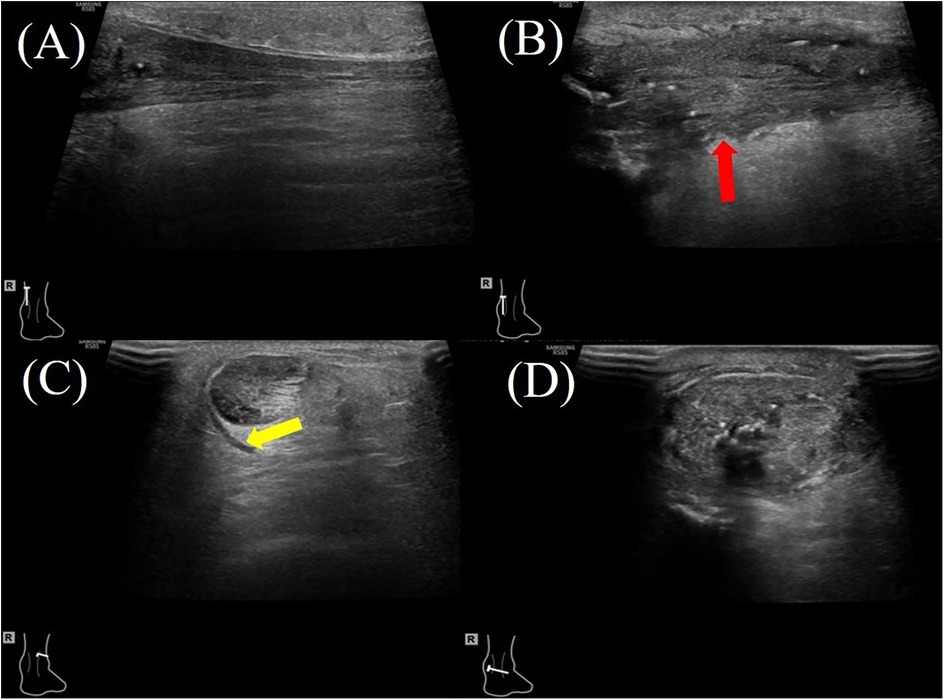

The hAM, composed of multiple collagen types (I, III, V, VI), amniotic epithelial cells, and MSCs, secretes a wide range of bioactive cytokines and growth factors (e.g., TGF-β1, PDGF, IGF, IL-1, IL-10), which contribute to its anti-inflammatory, anti-fibrotic, and regenerative properties (6, 8, 20). In animal models, amniotic membrane application to Achilles tendon injuries has been shown to reduce inflammatory cell infiltration, improve type I and III collagen organization, and significantly enhance biomechanical properties such as tensile strength, stiffness, and cross-sectional area (25, 26) (Figures 2, 3). In contrast, the hAM allograft used in the present study was an acellular, non-vital material, which differs in biological composition from the materials evaluated in previous studies and may therefore not be directly comparable (25, 26). Further studies are needed to determine whether these differences influence clinical outcomes.

Figure 2. A 47-year-old female patient with right Achilles tendon rupture located 3.3 cm proximal to the calcaneal insertion underwent surgical repair with hAM augmentation. At the 2-month postoperative follow-up, ultrasound evaluation showed: (A) the proximal healthy tendon on the longitudinal plane showing a homogeneous echotexture. (B) the repair site (red arrow) on the longitudinal plane demonstrating mild heterogeneity in echotexture and variable tendon thickness; (C) the proximal healthy tendon on the transverse plane with a small amount of surrounding inflammatory effusion (yellow arrow). (D) the repaired tendon on the transverse plane, demonstrating increased cross-sectional area.